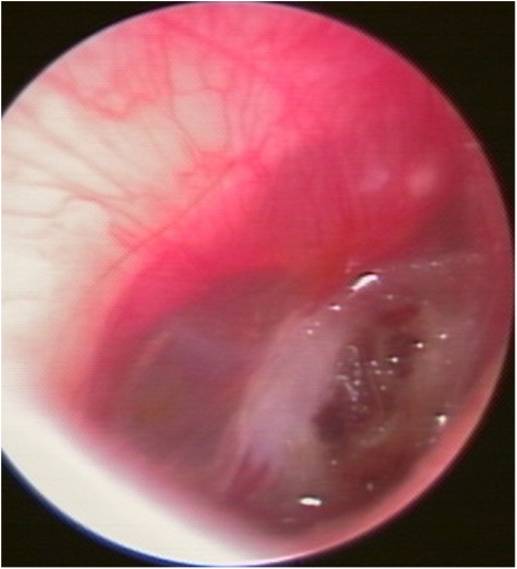

这是耳朵鼓膜穿孔的声镜照片 有谁懂得帮我看下严

图片尺寸780x1040